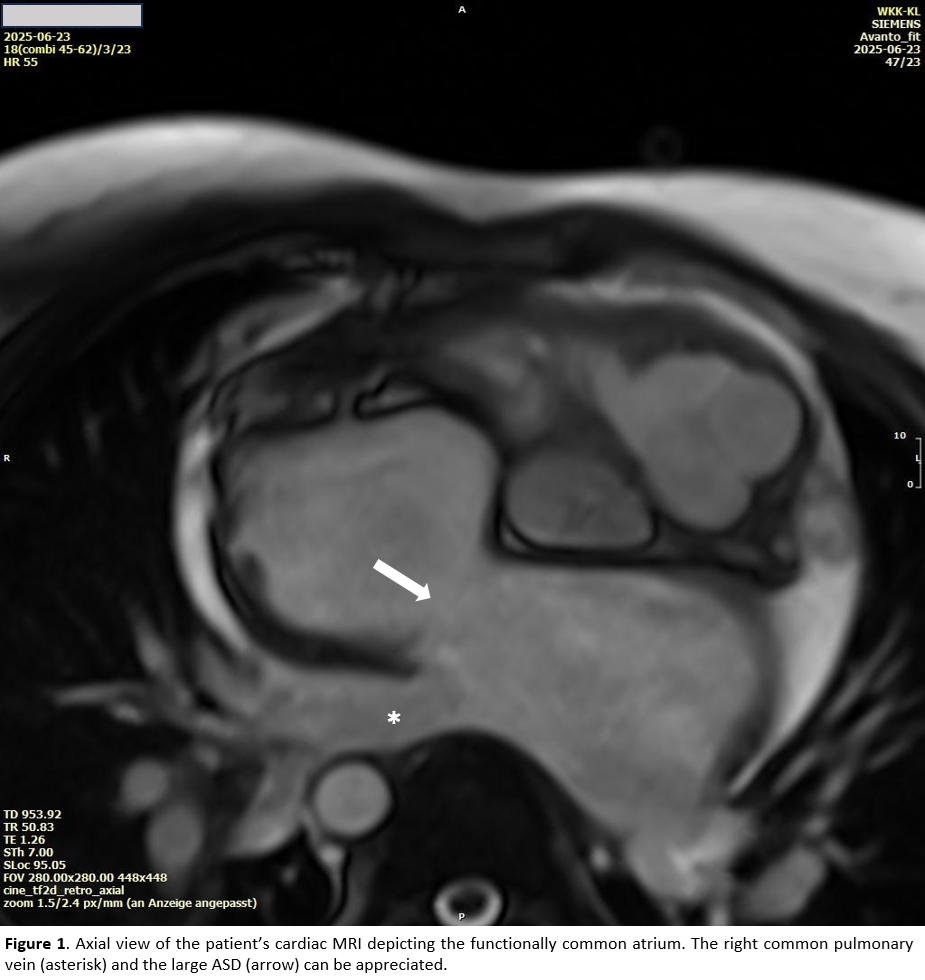

The patient's cardiac anatomy was consistent with a classic DILV featuring a functional single ventricle and ventriculo-arterial discordance. Additional findings included a large atrial septal defect (ASD) with a functional common atrium and a common right pulmonary vein (RCPV). Pre-procedural evaluation comprised an MRI and right-heart catheterization.

Electroanatomic mapping was performed with the EnSite™ NavX™. A significant medial shift of the left atrial sagittal axis was observed, along with a leftward and caudal displacement of the left atrial appendage. In nearly most of the left atrium, endocardial bipolar voltage was <1.5 mV, with only scattered low-voltage areas (LVA) <0.5 mV. The lateral pulmonary veins demonstrated preserved antral conduction, likely reflecting a previously deep balloon position. On the septal aspect, conduction into the RCPV was fully preserved.